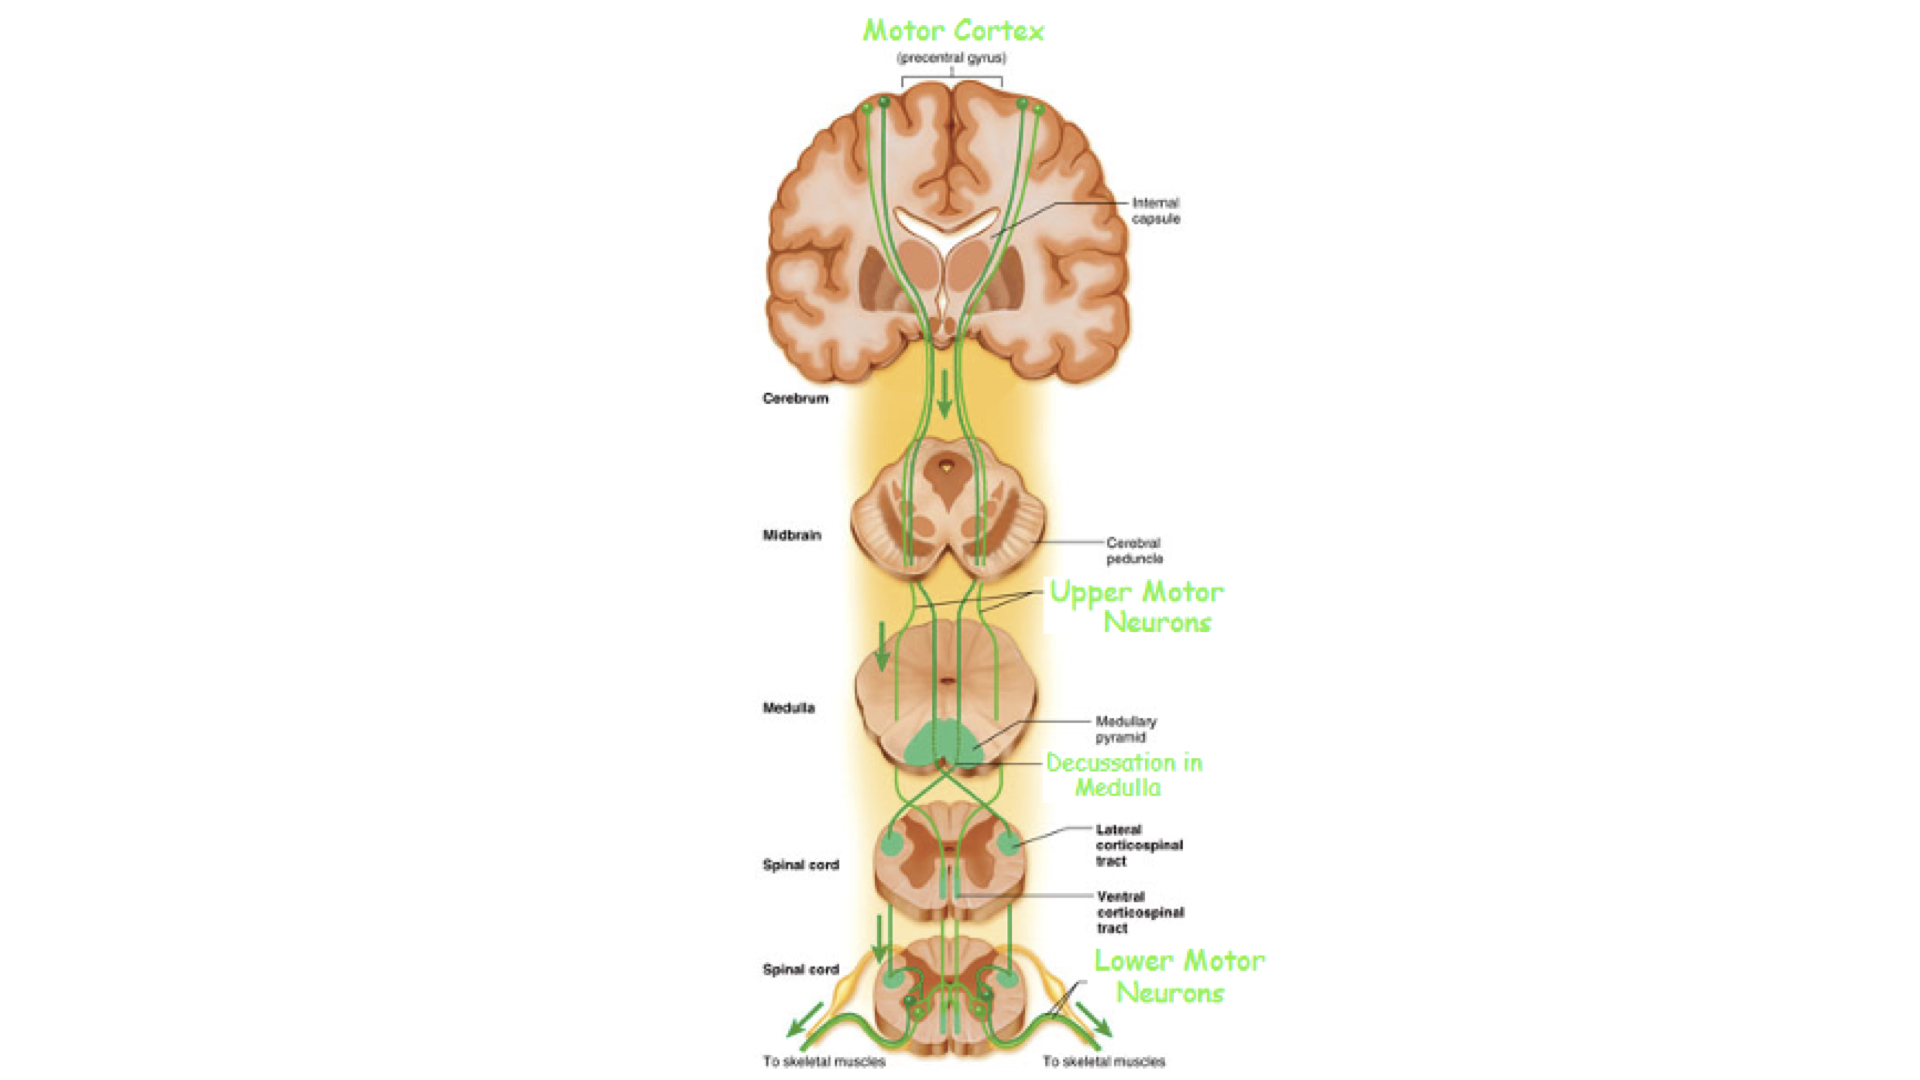

2. Descending pathways have only two neurons between cerebral cortex and effector organ.

f. Decussation simply means the cross over between right and left. Remember that sensory data from right side of body and motor responses to the right side of the body involve the left cerebral hemisphere. Sensory and motor data from and to the left side of the body involve the right cerebral hemisphere.